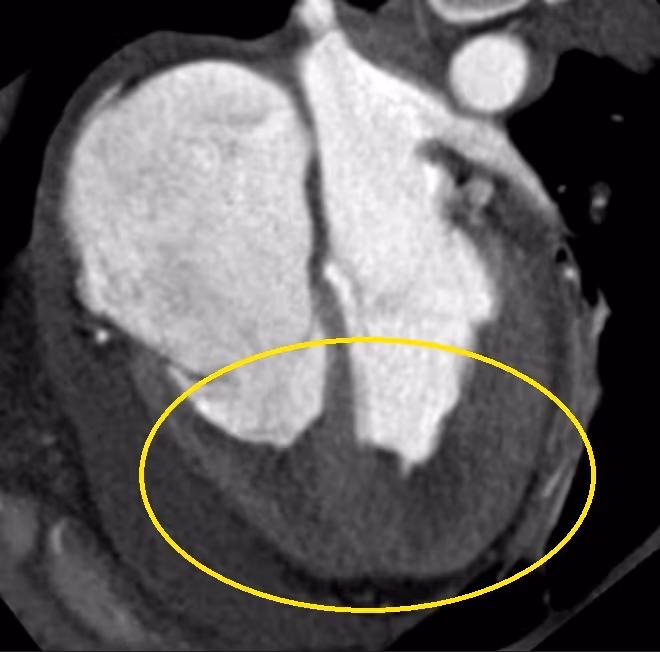

Ventricular septal rupture as a complication of subacute myocardial infarction

2021-02-01

in

Clinical Cases